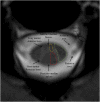

Background: Vascular lesions of the spinal cord are rare but potentially devastating conditions whose accurate recognition critically determines the clinical outcome. Several conditions lead to myelopathy due to either arterial ischemia, venous congestion or bleeding within the cord. The clinical presentation varies, according with the different aetiology and mechanism of damage.

Purpose: The aim is to provide a comprehensive review on the radiological features of the most common vascular myelopathies, passing through the knowledge of the vascular spinal anatomy and the clinical aspects of the different aetiologies, which is crucial to promptly address the diagnosis and the radiological assessment.